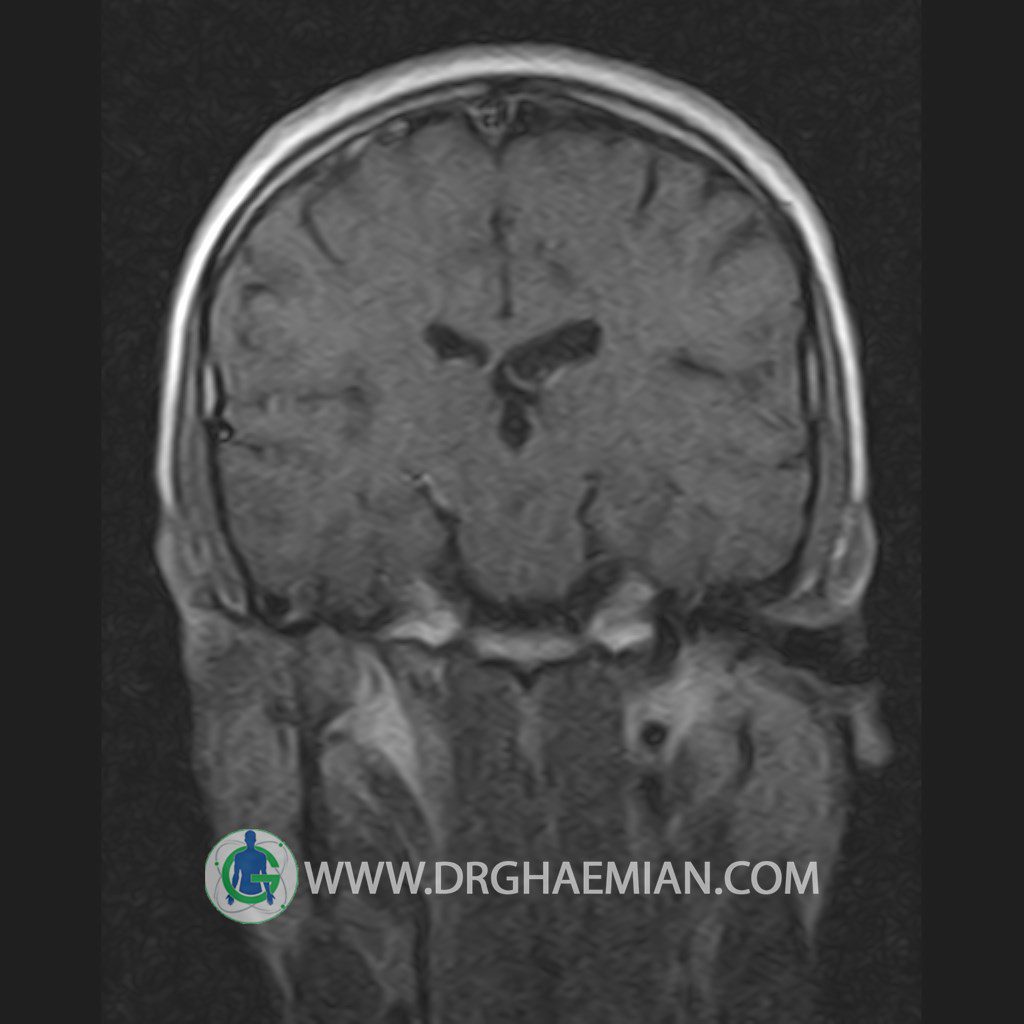

پزشکان اغلب از تصویربرداری ام آر آی برای تشخیص و درمان عارضه های پزشکی که فقط با استفاده از اشعه ایکس یا میدان مغناطیسی و امواج رادیویی قابل مشاهده است، استفاده می کنند. دستگاه ام آر آی تصاویر دقیق از ساختار های داخلی بدن ایجاد می کند. در این کیس یک میکروآدنوم در هیپوفیز بیمار مشاهده می شود.

HYPOPHYSIS MRI

(with and without contrast)

Technique: Axial , coronal T1 , Axial , coronal , sagittal T2 , Axial, coronal T1 post Gd & 64 dynamic thin coronal slices.

REPORT :

The infundibulum is centered and of normal size .

The optic chiasm and suprasellar spaces appear normal .

The cavernous sinus and imaged portions of the internal carotid artery and carotid siphon are unremarkable .

Evaluable portions of the neurocranium show no abnormalities .

The sphenoid sinus is clear and pneumatized .

Imaging of the hypothalamus after contrast medium administration was normal.

– Small hypoenhancing mass lesion ( 3 x 4 mm ) in posterior of pituitary stalk suggestive for micro adenoma

– Mucosal thickening in ethmoid & maxillary sinuses

is seen